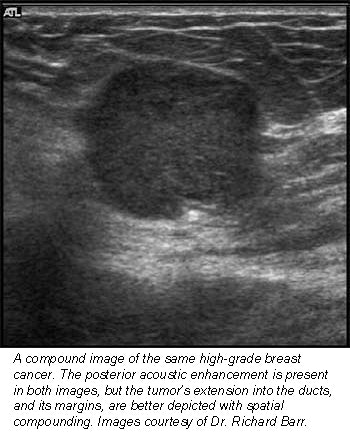

In the random analysis, viewers rated 91% of the compound images excellent in terms of margin definition, as well as near-field, lesion, and anatomic details. In the comparative analysis, compound ultrasound rated similar to conventional ultrasound in 82% of patients in depicting near-field detail and small structures such as ducts. And it rated better than conventional ultrasound in all patients for margin and lesion definition, as well as reduced speckle.

"Now, we can see if a tumor has advanced into a duct," Barr said. "Sometimes, these things are very small, and only with compound imaging can you tell if something is clutter noise or if it’s real."